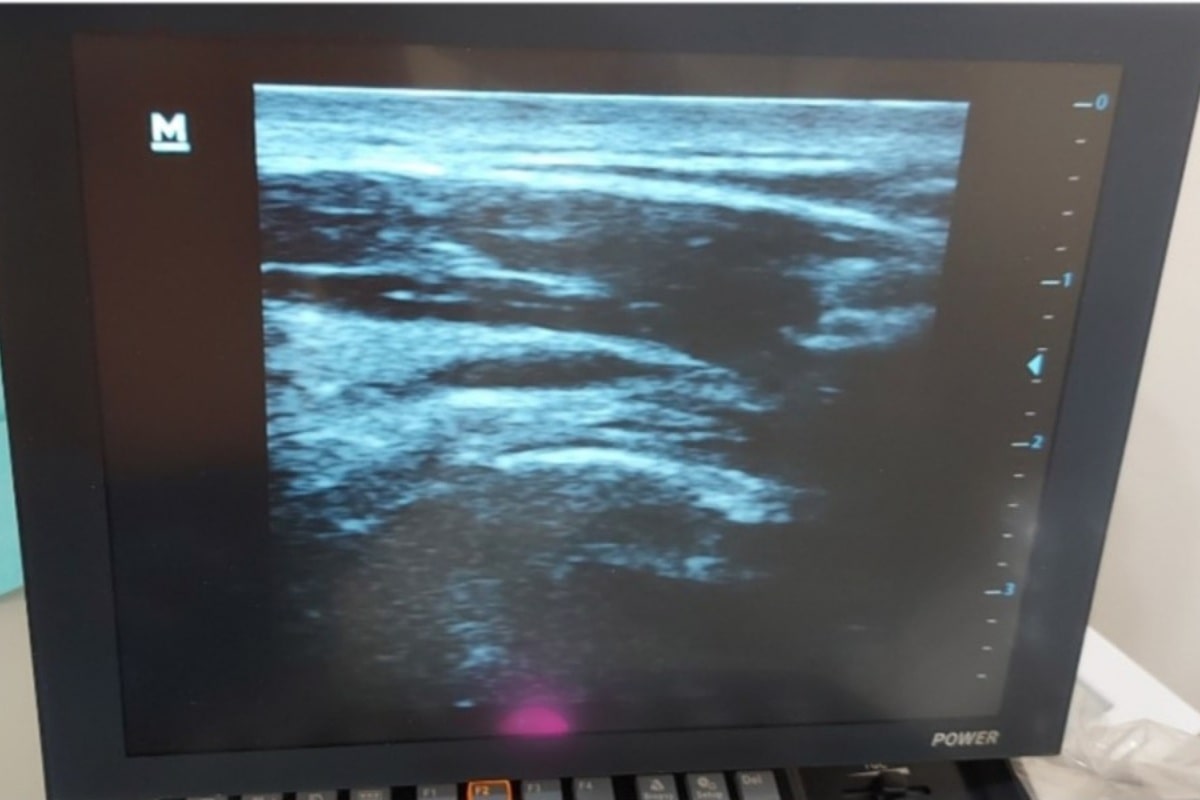

Επιβεβαιώνεται με απεικονιστικές μεθόδους της μαγνητικής τομογραφίας και του υπέρηχου του ώμου.